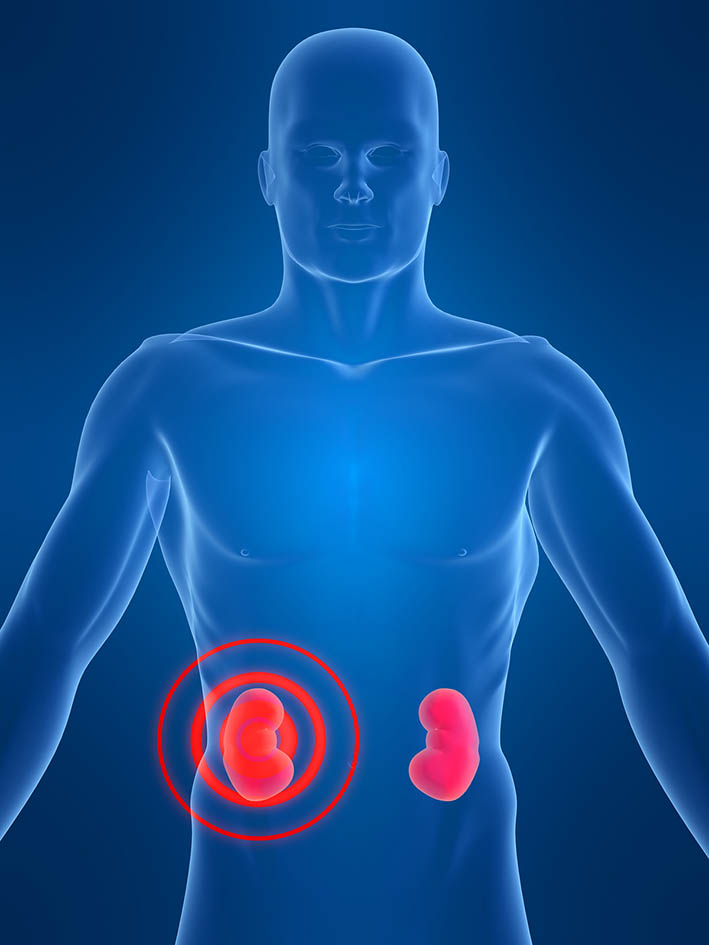

عکس کلیه در بدن. اگر پشت یا پهلوی شما آسیب ببیند مثل برخورد ضربه ممکن است فکر کنید که کلیه هایتان درد می کنند. مقدار و نسبت ترکیب این اخلاط در بدن هر شخصی و در اندامهای. کلیه گ رده ها1 از اندام های درونی بدن انسان به صورت یک جفت عضو لوبیایی شکل در طرفین ستون فقرات روی جدار پشتی شکم و بیرون از حفره صفاق قرار دارند. ک لیه ق لوه میز یا گ رده یکی از اندام های درونی بدن انسان و برخی دیگر از جانداران است.

کلسیم و فسفر که برای تشکلی استخوان لازمند کمک می کنند مواد. کلیه ها با تولید ادارد در دفع مواد زاید تعادل الکترولیتی تنظیم هورمونی تنظیم فشار خون و هوموستازگلوکز نقش دارند. آناتومی کلیه انسان در بدن انسان به این شکل است که کلیه ها دو عضو لوبیایی شکل در دستگاه ادراری بوده و به دفع مواد زائد به صورت ادرار کمک می کنند. یکی از مهم ترین وظایفی که کلیه ها در بدن بر عهده دارند پاک کردن و تصفیه خون از زباله هاست.